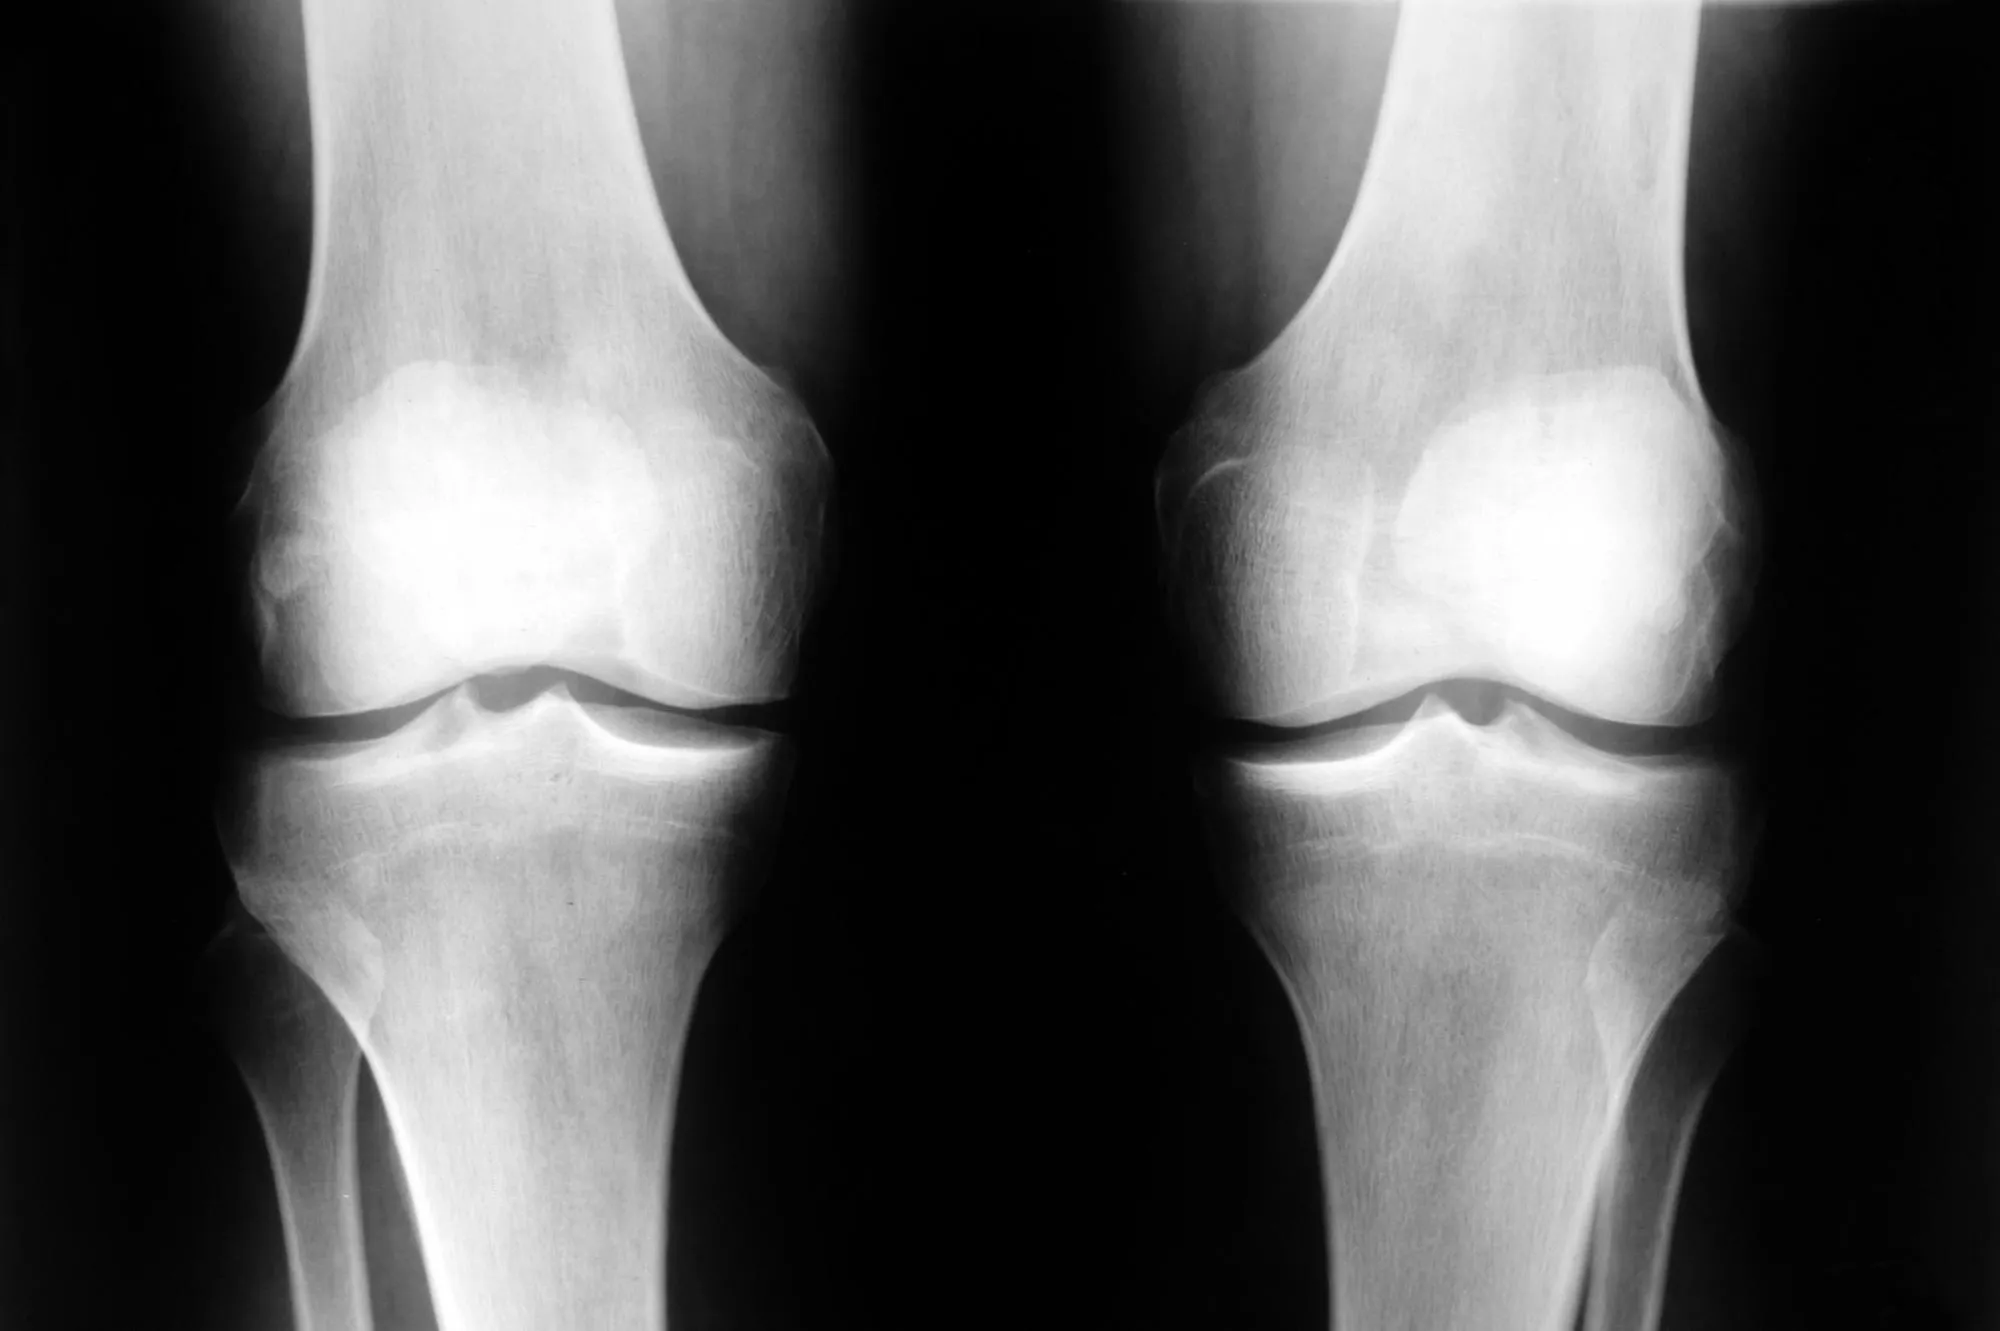

Pourquoi : en cas d’arthrose, le cartilage de l'articulation, ce revêtement protecteur qui protège les extrémités osseuses, n'est plus nourri correctement par le sang et finit par s'éroder jusqu'à disparaître complètement par endroit, mettant l'os à nu. L'espace entre les têtes osseuses de l'articulation se rétrécissant par manque de cartilage, les os finissent par frotter l'un contre l'autre, entraînant la douleur.

Les manifestations : des excroissances osseuses sous la peau, voire des déformations de l'articulation toute entière peuvent apparaître. Ces déformations sont irréversibles.

Pourquoi : les "déformations" osseuses sont secondaires à une hyperactivité osseuse déclenchée par la destruction du cartilage. C'est la production d'ostéophytes.